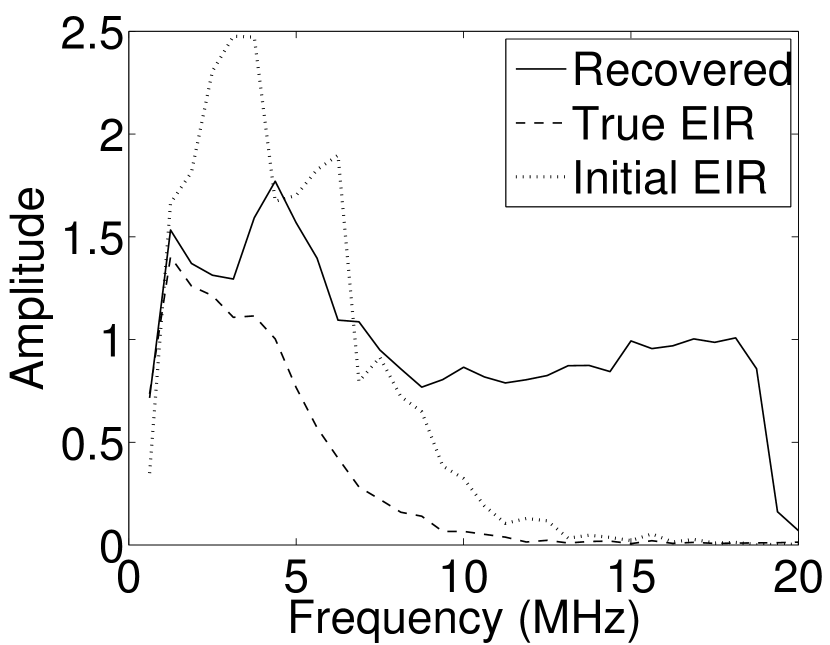

As shown in Figure 6, when the error in the EIR was small (e.g., as with the EIR in Figure 6(a)), images were reconstructed with high accuracy using the VP algorithm. When the perturbations in the EIR were stronger (e.g, as in Figure 6(c)), artifacts and distortions in the reconstructed images were still significantly reduced by use of the VP algorithm; however, larger values of the regularization parameters had to be applied. When as in the initial EIR in Figure 6(e), no improvement was observed in the image reconstructed by use of the VP algorithm.

Images reconstructed by use of the VP algorithm with different values of the regularization parameter values are shown in Figure 8. The recovered EIRs and their corresponding Fourier spectra are shown in Figures 9 and 10, respectively. The RMSE values are computed and displayed together with the corresponding images. As expected, the images reconstructed with smaller values of contain higher noise levels, while images using larger possess a reduced noise level. However, larger values of also caused artifacts in the reconstructed images. The same observation can be made for the effect of the regularization parameter on the recovered EIR. One also observes that the reconstructed images and EIRs depend continuously on the regularization parameters and , i.e. small changes in the regularization parameters cause minor changes in the reconstructed images and EIRs.